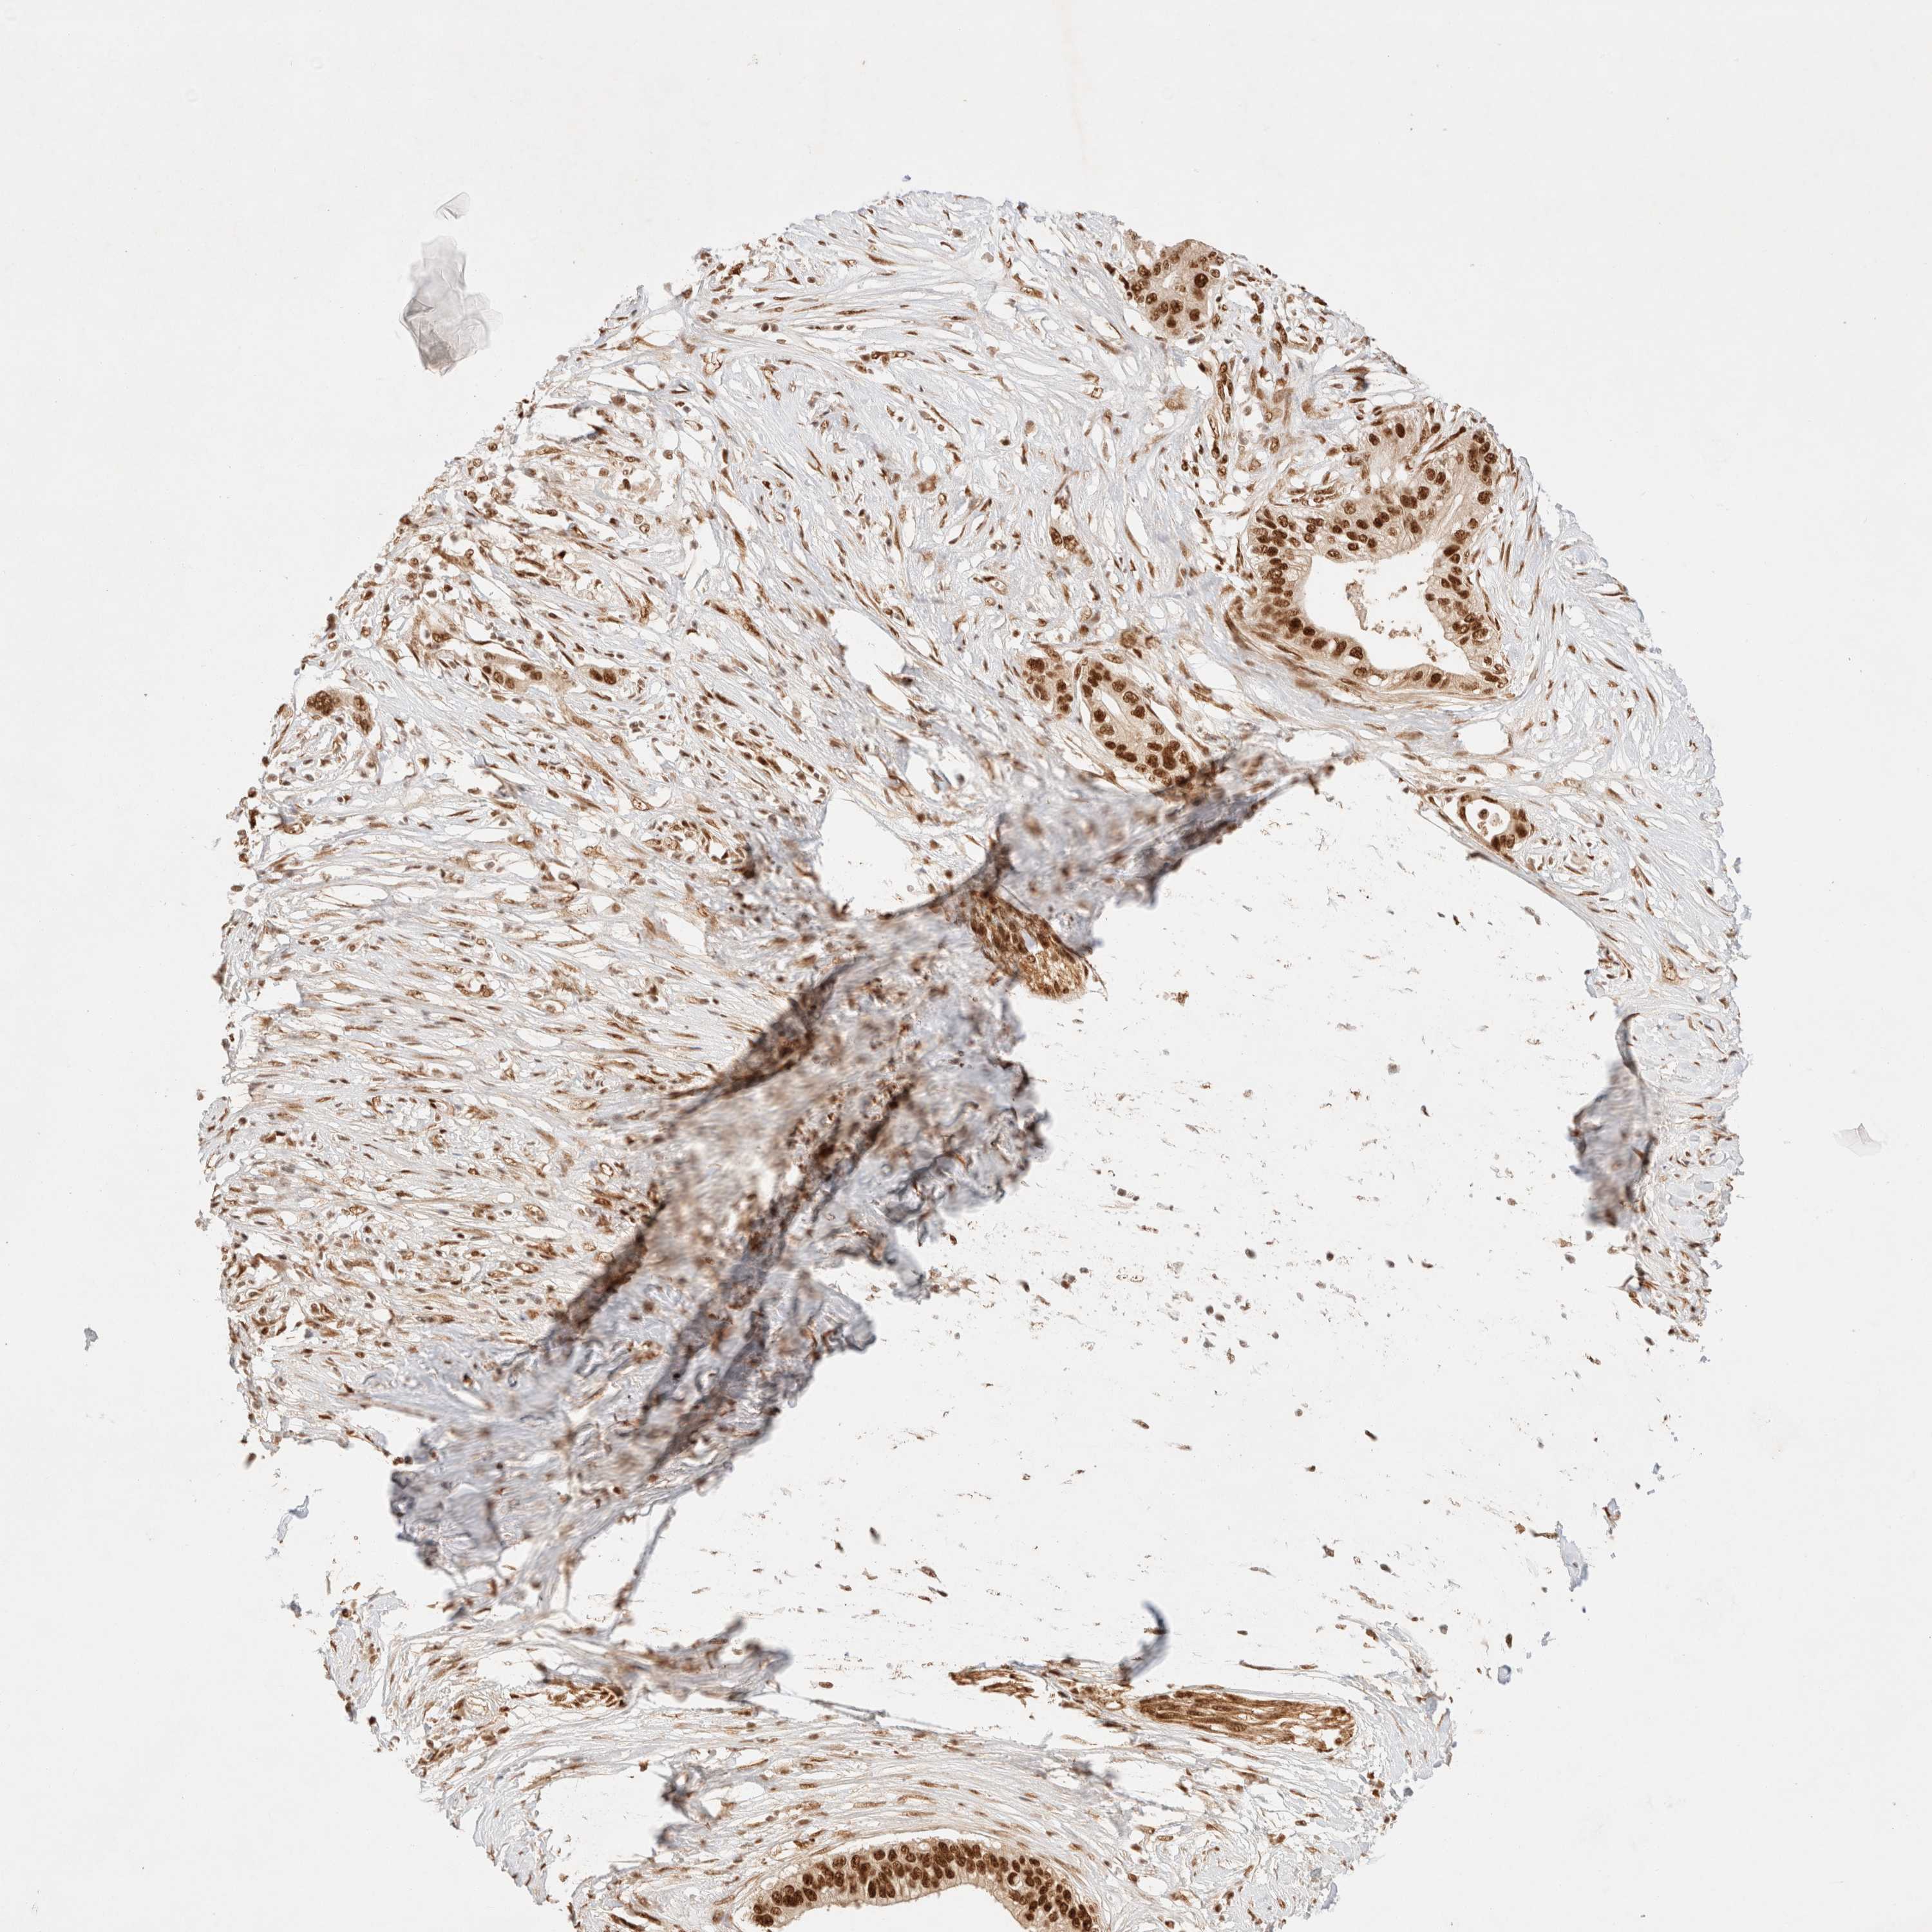

PANCREATIC CANCER - Protein expressioni

A mouse-over function shows sample information and annotation data. Click on an image to view it in a full screen mode. Samples can be filtered based on level of antibody staining by selecting one or several of the following categories: high, medium, low and not detected. The assay and annotation is described here.

Note that samples used for immunohistochemistry by the Human Protein Atlas do not correspond to samples in the TCGA dataset.

Antibody stainingi

Antibody staining in the annotated cell types in the current human tissue is reported as not detected, low, medium, or high, based on conventional immunohistochemistry profiling in selected tissues. This score is based on the combination of the staining intensity and fraction of stained cells.

Each image is clickable and will lead to virtual microscopy that enables deeper exploration of all samples and also displays staining intensity scores, fraction scores and subcellular localization as well as patient and tissue information for each sample.

Antibody HPA024630

Staining

High

Medium

Low

Not detected

Intensity

Strong

Moderate

Weak

Negative

Quantity

>75%

75%-25%

<25%

None

Location

Nuclear

Cytoplasmic/membranous

Cytoplasmic/membranous,nuclear

Adenocarcinoma, NOS